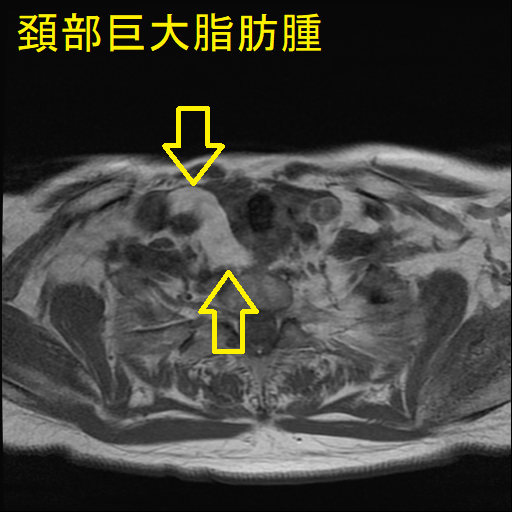

巨大頚部脂肪腫

血管脂肪腫は脂肪腫の一種で脂肪と血管を含みます。20歳から30歳までの若年成人に発症し、その原因として、

ほとんどが前腕ですが、頚部に現れる場合もあります。痛みを伴う点が脂肪腫と異なり、脂肪肉腫とも鑑別を要します。[Skeletal Radiol. 2023 Mar;52(3):541-552.]